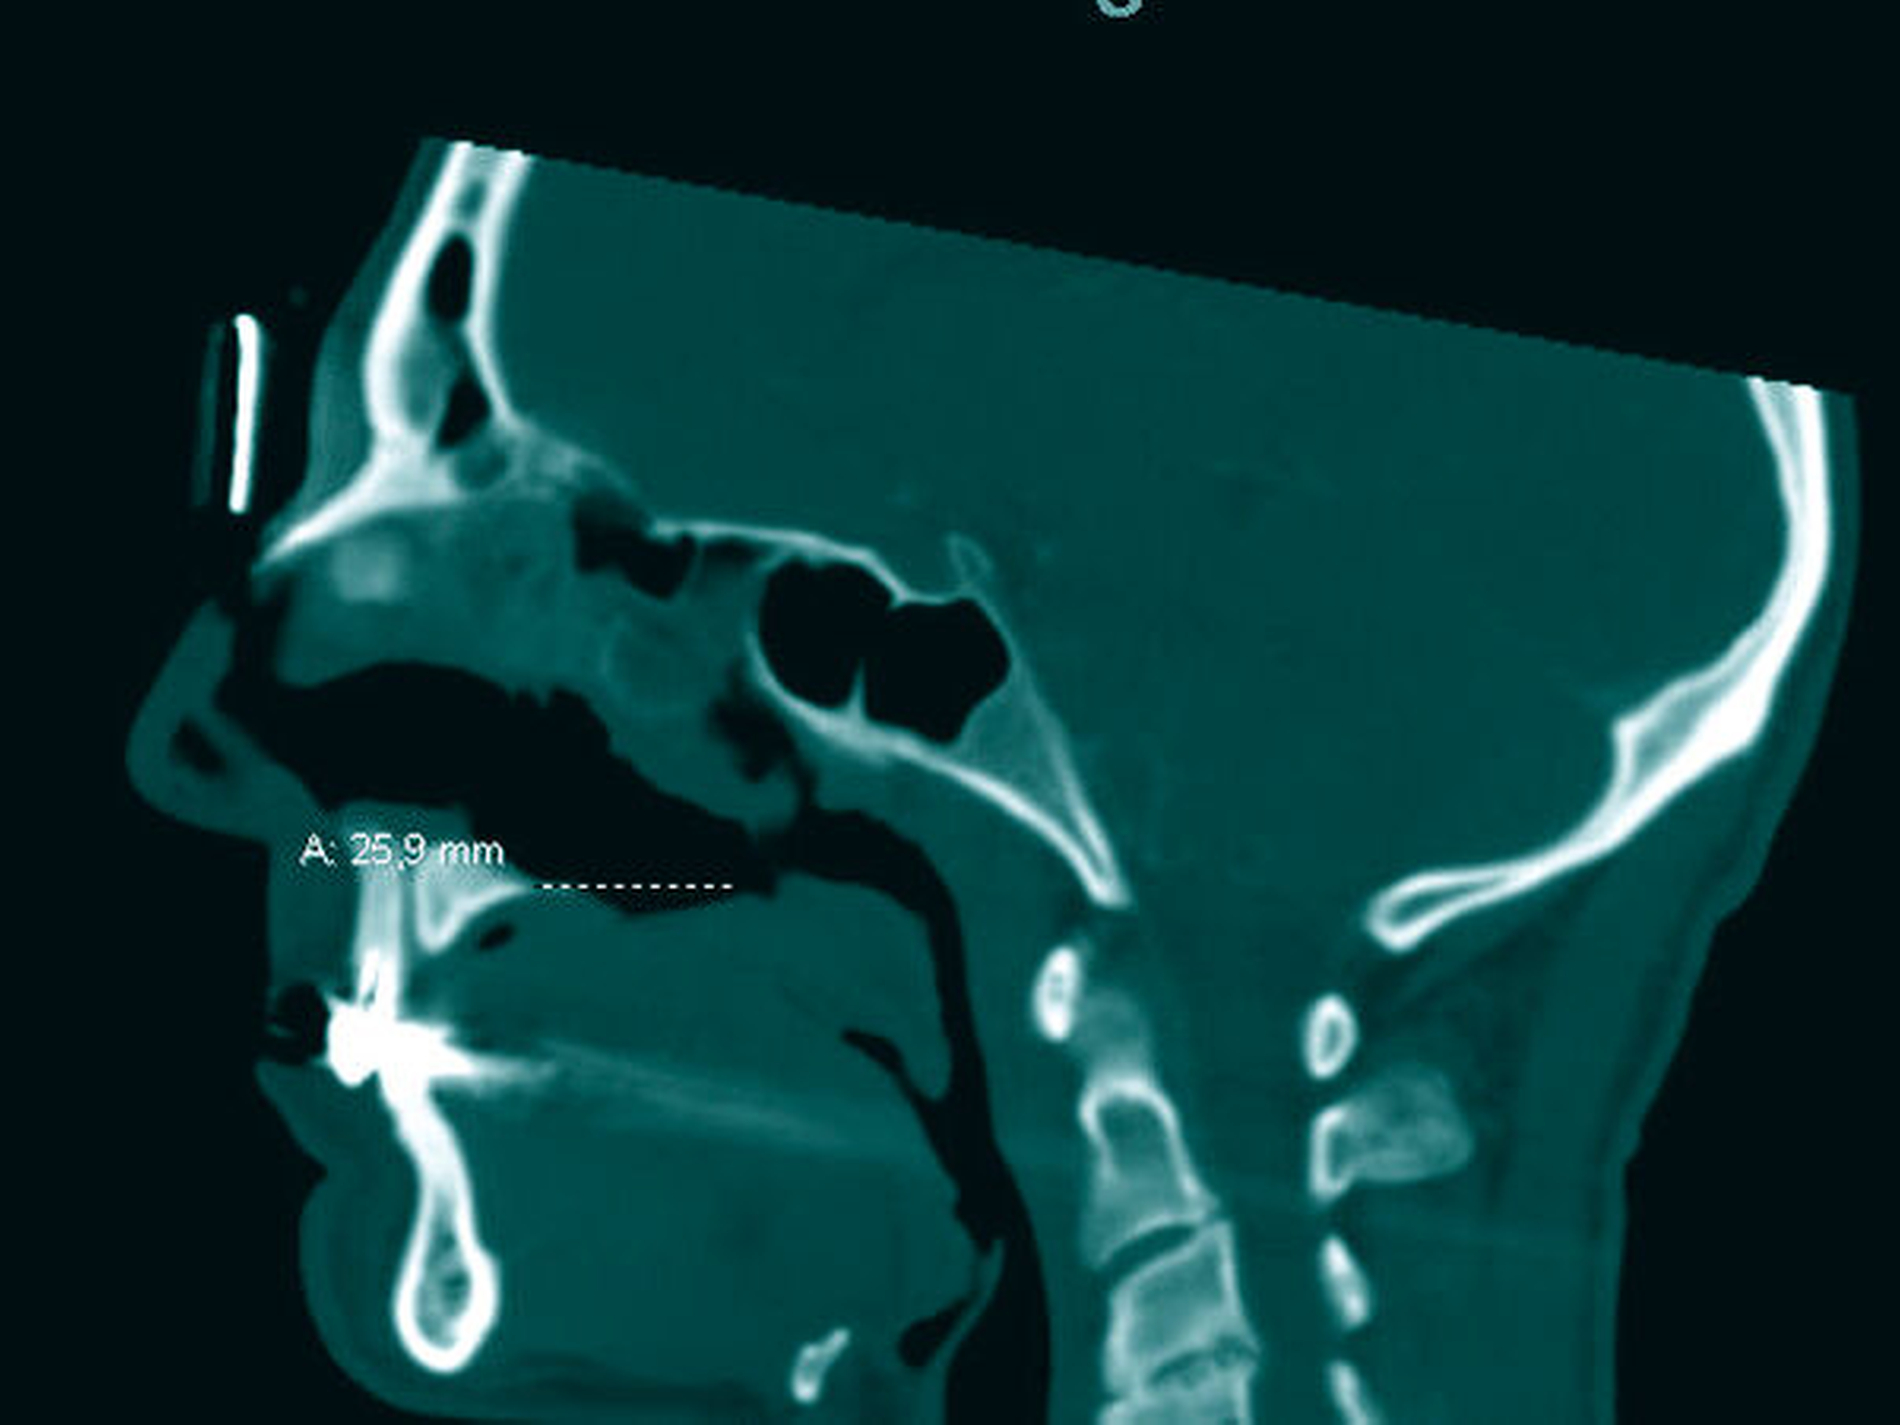

Es folgten eine Blutabnahme mit Routinelabor und Serologie (Lues, HIV, Hepatitis C) sowie eine Alginatabformung zur Herstellung einer Tiefziehschiene. Der Patient wurde zur weiteren Planung und Schieneneingliederung am Folgetag einbestellt. Nach einer raschen CT-Untersuchung mit Kontrastmittel Kopf/Hals (Abbildungen 1 bis 3) erfolgte eine endoskopische Rhinoskopie mit bioptischer Sicherung in ITN unter stationären Bedingungen.

CT-Befund Kopf/Hals: Weichteil-dichte Raumforderung im Bereich der linksseitigen Ethmoidalzellen, vollständige Verlegung des Sinus frontalis links sowie teilweise Verlegung rechtsseitig; zirkuläre Schleimhautschwellung in beiden Sinus maxillaris bei ausgedehnter Destruktion von Nasenseptum, Nasenmuscheln, der medialen Sinuswände und des Hartgaumens sowie subtotal verlegte linke Mastoidzellen bei regelrechter Belüftung vom Mittelohr beiderseits.